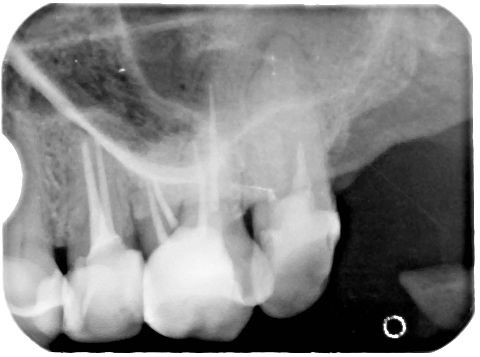

Jeszcze w stosunkowo niedalekiej przeszłości pokutowało wśród pacjentów (i niestety również wśród niektórych lekarzy dentystów) przekonanie, że zęby będące przyczyną stanów ropnych należy usunąć. Tymczasem można te zmiany skutecznie leczyć, a aktywny wysięk opanować czasami zaledwie w trakcie kilku dni (ryc. 9‑11). Dopiero w przypadku niepowodzenia terapii zachowawczej należy rozpatrzyć zastosowanie zabiegu endodontyczno‑chirurgicznego lub w skrajnych przypadkach usunięcie zęba. W wielu przypadkach można też przeprowadzić leczenie jednowizytowe, nawet jeśli występują przewlekłe zmiany zapalne w tkankach okołowierzchołkowych (20‑23). Gdy leczenie na jednej wizycie jest niemożliwe, najczęściej zaleca się stosowanie opatrunku na bazie wodorotlenku wapnia. Działanie lecznicze preparatów wodorotlenkowo‑wapniowych jest związane z ich wysokim pH oraz z uwalnianiem jonów wapniowych i hydroksylowych (21, 23). Jony hydroksylowe powodują obniżenie ciśnienia tlenu i wzrost pH w tkankach zmienionych zapalnie. Jony wapniowe stymulują fosfatazę zasadową do wytwarzania zębiny i naprawy kości oraz wpływają na miejscowe reakcje immunologiczne. Niskie ciśnienie i alkaliczne środowisko sprzyjają procesom mineralizacji naprawy. Bakteriobójcze działanie wodorotlenku wapnia polega na niszczeniu cytoplazmatycznej błony komórek bakteryjnych oraz destrukcji struktur białkowych i DNA (23).

Ryc. 9. Przetoka czynna w przedsionku jamy ustnej, zlokalizowana w okolicy zębów 41-42.

Źródło: Olczak K, Pawlicka H. Zastosowanie rentgenodiagnostyki w endodoncji. Mag Stomatol. 2019; 9: 30.

Ryc. 10. Zdjęcie rentgenowskie zęba 31 oraz umieszczonego w przetoce ćwieka gutaperkowego.

Ryc. 11. Zastosowano antyseptyczne leczenie kanałowe zęba 31. Po tygodniu przetoka uległa wygojeniu.